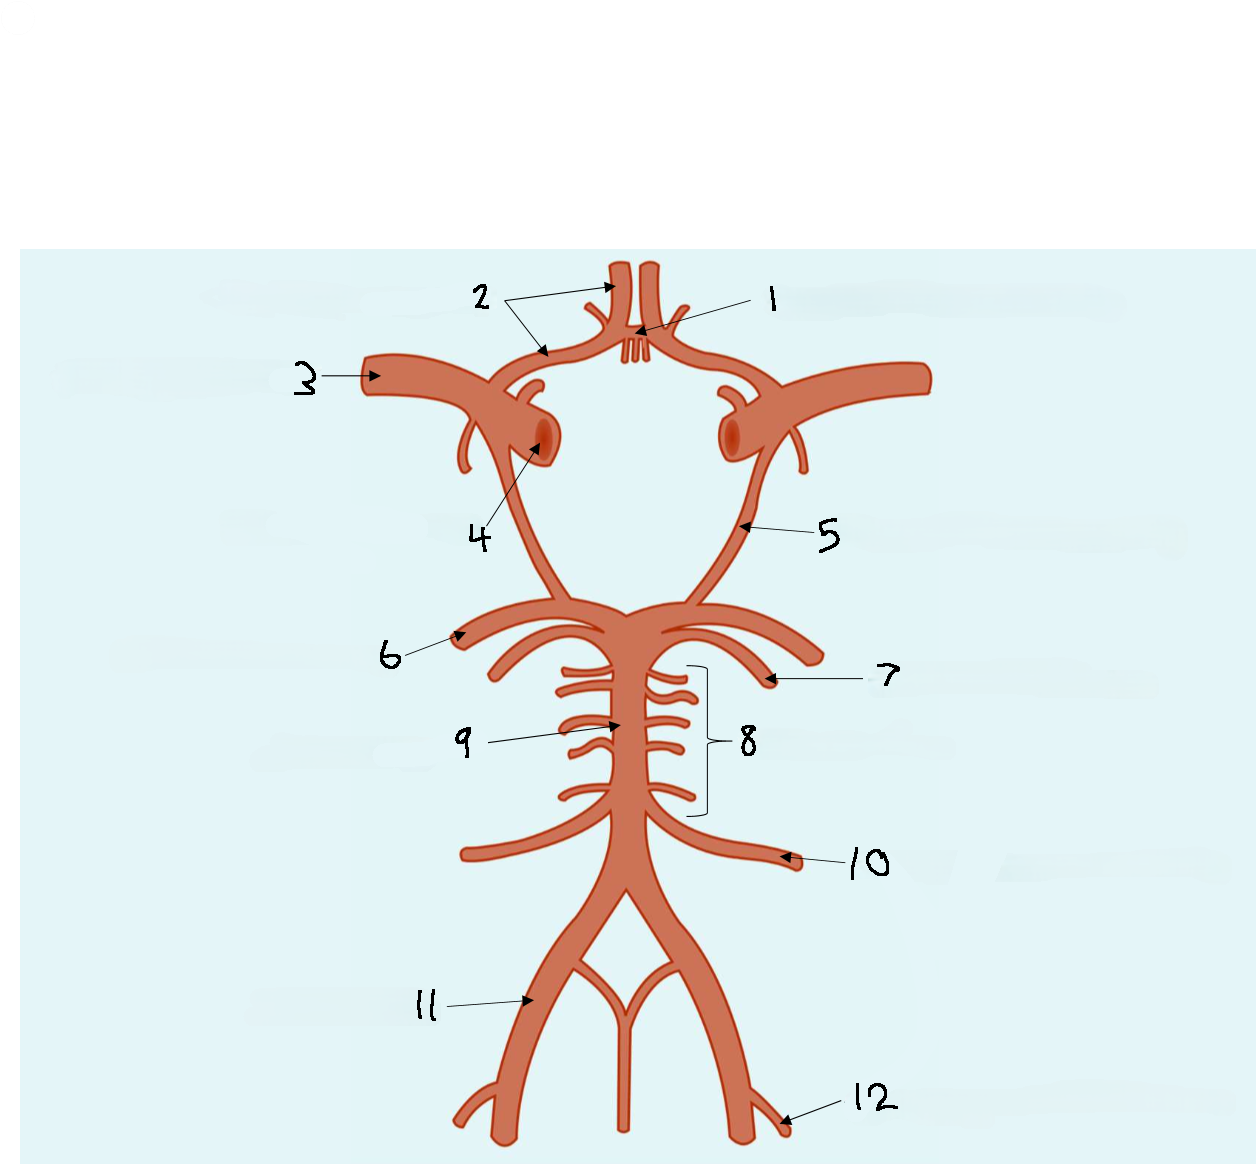

What is 1?

anterior communicating artery

What is 2?

anterior cerebral artery

What is 3?

middle cerebral artery

What is 4?

internal carotid artery

What is 5?

posterior communicating artery

What is 6?

posterior cerebral artery

What is 7?

superior cerebellar artery

What is 8?

pontine arteries

What is 9?

basilar artery

What is 10?

anterior inferior cerebellar artery

What is 11?

vertebral artery

What is 12?

posterior inferior cerebellar artery